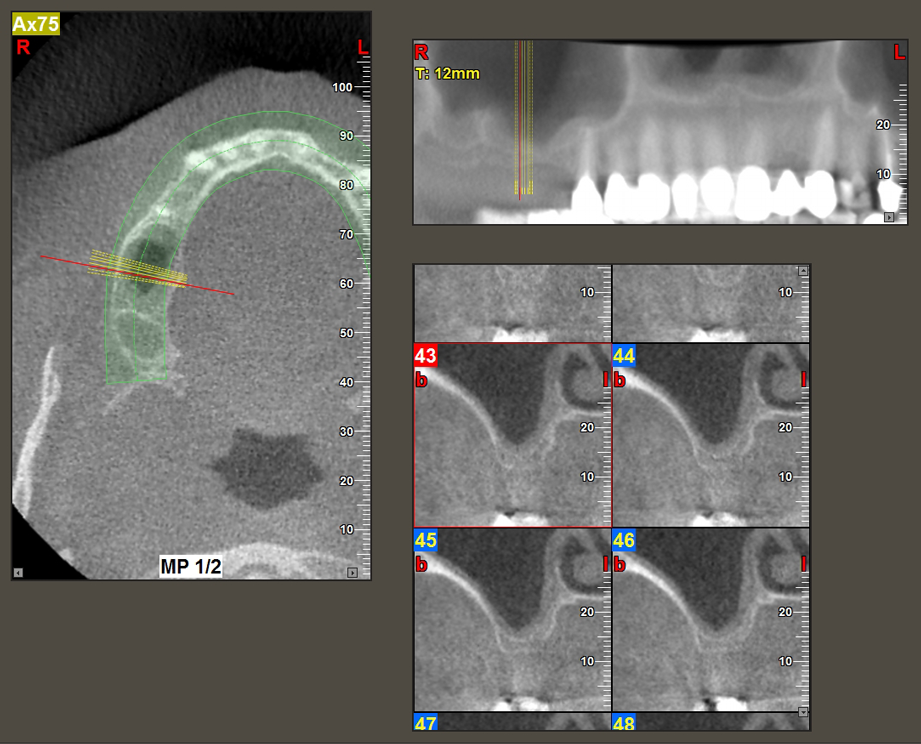

49-летняя пациентка, некурящая и не имеющая ничего примечательного в общей истории болезни, была направлена в нашу хирургическую стоматологическую клинику для хирургического удаления зуба 16 и последующей имплантации. После удаления зуба пациентка перенесла синусит в легкой форме, в результате чего мы сначала выждали шесть месяцев перед проведением операции. Остаточная высота кости при запланированном положении имплантата составляла 3-4 мм (рис. 1 и 2).